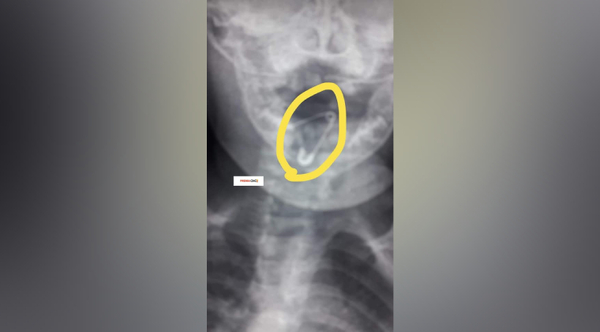

Diario HOY | Retiran con éxito prendedor de alfiler atascado en la garganta de una bebé

La única cirujana pediátrica de Coronel Oviedo se encontraba en un evento social por su día libre, pero asistió al hospital para asistir a la bebé logrando evitar una perforación y hemorragia. ...[Leer más]